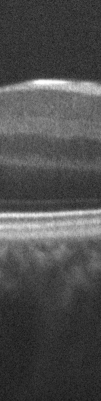

Fig. 4: A portion of one of the input images (a) and the results of ImageJ translation (b), ImageJ rigid (c) and RASL rigid registration based methods.